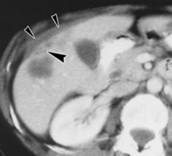

Một phụ nữ 47 tuổi đến viện sau khi đã qua 2 cơn đau bụng phía bên phải. Bà ta không có tiền sử sốt, không có gan lớn qua thăm khám thực thể. Bà ta không bị sốt, không có gan lớn sau khi thăm khám lâm sàng. Các dữ liệu xét nghiệm về sinh hóa, huyết học và tế bào đều cho kết quả bình thường, ngoại trừ có tăng bạch cầu eosin lên đến 11%. Chụp CT scan cho thấy các hình ảnh giảm âm nhiều ổ trên khắp bề mặt gan của bệnh nhân. Một hình ảnh abcès hoại tử nằm ở vùng trước của gan phải, góc và có hình ảnh các nốt giảm âm. Các tổn thương có hình ảnh dạng nốt hoại tử, bờ vằn vèo như xoắn, cả ở vị trí dưới bao gan và nghi ngờ là sán lá gan lớn. Tiến hành chọc sinh thiết bằng kim nhỏ nhằm nghiên cứu về góc độ tế bào kết quả cho thấy hình ảnh hoịa tử xuất huyết và thâm nhiễm các tế bào viêm lymphocyte và tăng số bạch cầu đáng kể, một trong số chúng là các bạch cầu ái toan. Chọc lấy dịch một phần từ ổ dịch dưới bao gan cho thấy hình ảnh dịch màu vàng đục không kèm theo máu. Phân tích tế bào học thì đây là các tế bào viêm của tổn thương nhu mô gan. Nuôi cấy dịch này không thấy xuất hiện tác nhân gây bệnh. Khi đặt ra vấn đề như vậy, hỏi đến tiền sử bệnh cho biết bà ta cũng thuowngf ăn rau cải xoong, tiến hành làm huyết thanh chẩn đoán dương tính Fasciola hepatica với hiệu giá 1/12.560. | Hình ảnh tổn thương gan do sán lá gan lớn trên phụ nữ 47 tuổi, hình ảnh chụp CT scan cho thấy khối abces ngoại biên dưới bao gan (mũi tên), vong bao gan biến dạng. Khối abces nằm ở góc sát với tổn thương gan, dày lên ở vùng bao. |

F.hepatica phải đi xuyên qua bao gan Glisson từ khoang phúc mạc vào nhu mô gan. Do đó, bất kỳ khi nào gan bị liên quan, bao gan và vùng nhu mô gần bao gan cũng luôn luôn bị ảnh hưởng. 2 loại tổn thương gan và vùng dưới bao gan biểu hiện rõ có thể nhìn thấy rõ trên hình ảnh CT.

Loại tổn thương thứ nhất là chùm tổn thương gồm nhiều vùng chứa các nốt nhỏ giảm âm (hypodense nodular).

Loại tổn thương thứ 2 đặc hiệu hơn, loại tổn thương có hình ảnh giảm âm (hypodense), với các đường ngoằn nghoèo như hình con rắn trên phim chụp CT. Sự xuất hiện trên CT các hình ảnh bao gan dày và nhu mô gan giảm nhiều cũng được mô tả như thể hình ảnh CT của bệnh sán lá gan lớn đặc trưng. Một hình ảnh tụ máu dưới bao gan lớn đơn thuần sẽ không đặc trưng cho bệnh sán lá gan lớn. Một hình ảnh tụ máu dưới bao gan có xuất huyết có thể là một biến chứng trong giai đoạn sán xâm nhập. Trong trường hợp hiếm, chảy máu có thể đe dọa tính mạng bệnh nhân vì độ trầm trọng và khả năng chảy máu tái phát. Sự liên quan của u máu dưới bao gan kèm theo tăng bạch cầu ái toan tăng cao sẽ đề nghịhoặc là viêm đa động mạch nút (polyarteritis nodosa) hoặc sán lá gan giai đoạn xâm nhập. Trong giới hạn với sự hiểu biết của nhóm nghiên cứu, một tổn thương dưới bao gangây ra bởi sán lá gan lớn gây abces dường như hiếm khi được báo cáo trong y văn.